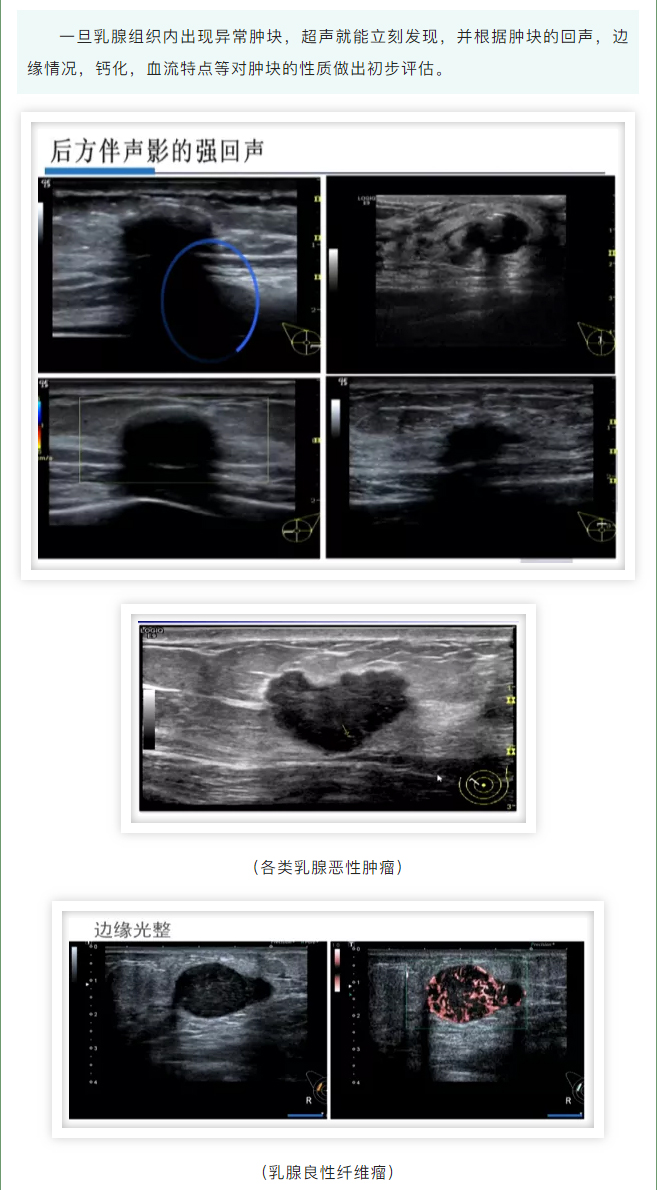

发现乳腺肿块,它俩帮了大忙!